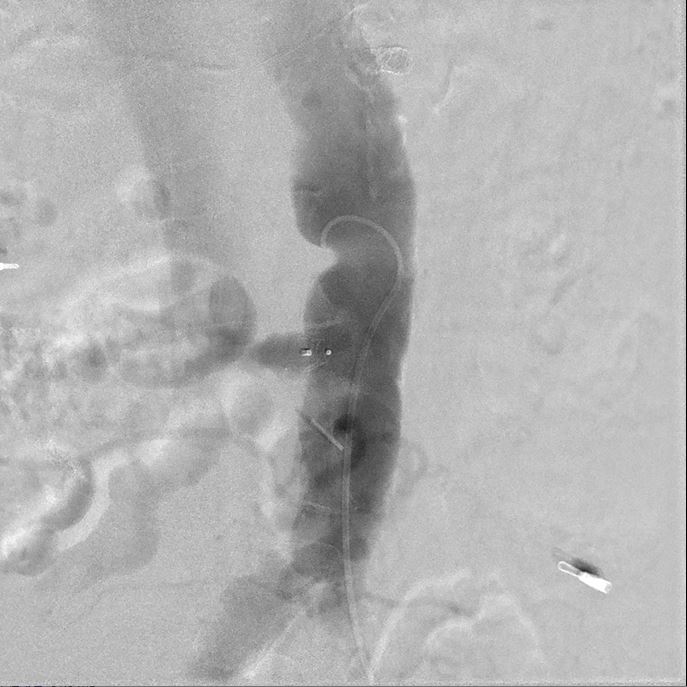

The transcaval approach starts with descending abdominal aortography. A 7-F renal double curve guide catheter which was advanced through the right femoral vein. An Astato wire along with a CXI microcatheter were advanced through the catheter to the indexed L3 level for transcaval puncture with the distal end of the Astato guidewire connecting with an electrosurgery pencil. After the Astato guidewire cross the vena cava and the adjacent aortic wall, the Asatato-CXI system was then captured by a 25 mm Gooseneck snare placed at the corresponding aortic level through left femoral atery, and sent upward to the thoracic aortic level. The Asatato wire was exchanged for a Lunderquist guidewire, through which an 20 French long sheath was advanced through RFV to the abdominal aorta. Standard TAVI procedures employing a Navitor 27 mm transcatheter heart valve were then performed through this vena-aortic connection facilitated by LV on-wire pacing. At the end of the procedure, an Amplatzer Duct Occluder was deployed to close the aorto-caval tract, with post-procedural angiography confirming a patent fistula with cruciform contrast flow around the neck of the occluder but with contrast returning to the cava. After careful examination, there was no extravasation on the digital subtraction angiogram. The next day, a follow-up angiogram of the aorto-caval fistula was performed, which revealed a patent fistula but without extravasation. The patient is doing well during one year of follow-up.